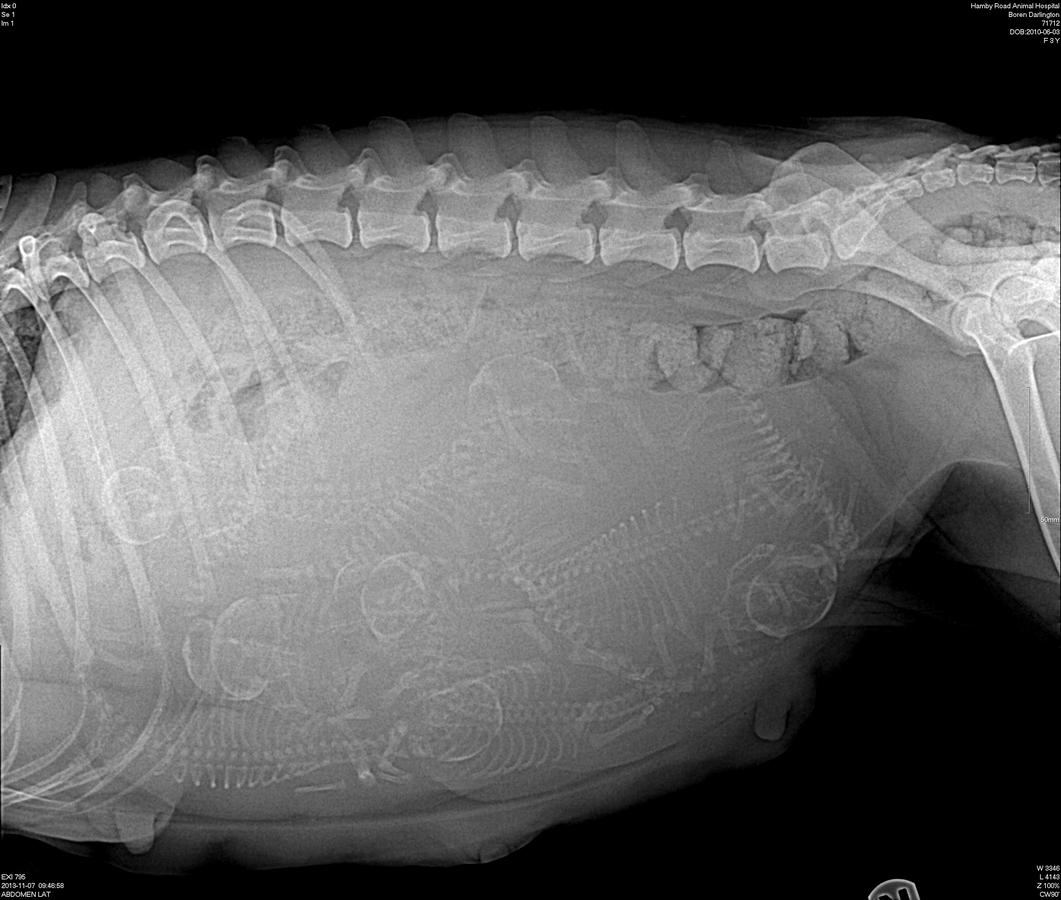

Darling preg xray day 59 preg 2

Excellent clarity on this xray, looks like possibly 8 counting skulls!